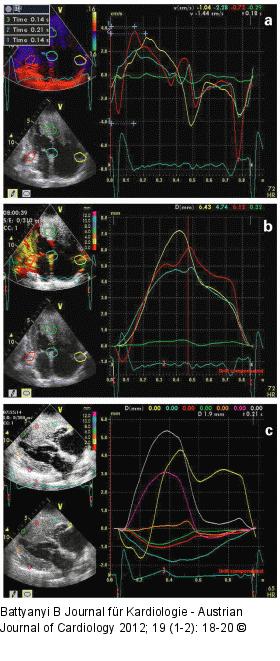

Abbildung 6a-c: Offline-TDI-Analyse Die Offline-TDI-Analyse zeigt Geschwindigkeiten (a) und Displacement (b) der ausgewählten Myokardregionen. (c): Displacement im PLAX-Anlotung. Das Septum und die infiltrierende Tumormasse bewegen sich nur gering. Die gemessene Zeiten in (a): (1.) Q-S lat., (2.) Q-S sept., (3.) Q-S RV lat., (4.) Dauer von QRS. Aufgrund der Erregungsausbreitungsstörung erreicht das rechte laterale Kammermyokard die maximale Geschwindigkeit, das Displacement etwa um 70 msec. später als das linke laterale Komponent. PLAX: parasternaler Längsschnitt. |